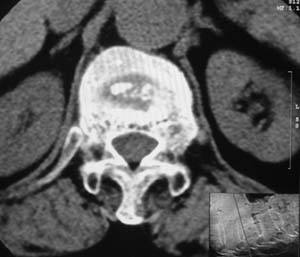

患者,女,72岁,胸背部疼痛3月余,无明显外伤史。曾应用局部封闭、非甾体类止痛药治疗效果不明显,近来疼痛缓解频感背困,平卧缓解,近日行ct检查发现胸12椎体病变,烦请同道发表意见,诊断什么?有何治疗经验!谢谢!!!

标绘图示:第十二胸椎级第一腰椎椎体楔形改变。ct扫描示:第十二胸椎椎体骨质结构紊乱,并可见一囊状低密度影,边缘可见硬化,椎体皮质完整。

考虑:第十二胸椎陈旧性骨折、许莫氏结节。